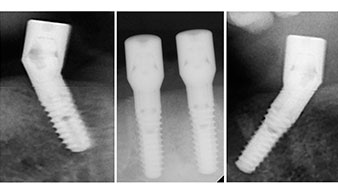

È stata eseguita una tomografia computerizzata Dentale Cone Beam in 3D (CBCT, con Planmeca) per aiutare la programmazione dell'intervento e la riduzione di rischi. L'esame ha evidenziato che la qualità e quantità dell'osso disponibile era sufficiente per eseguire l'intervento e la ricostruzione immediata, utilizzando il metodo Fast & Fixed. In base al protocollo del sistema, gli impianti sono stati inseriti in posizione 35, 32, 42 e 45. Gli impianti distali vengono installati a un angolo massimo di 45 gradi. Così facendo, il profilo che ne risulta viene spostato in posizione posteriore, generando un poligono di supporto più ampio (Fig. 3).

Il protocollo chirurgico per il sistema di implantologia utilizzato (SKY, Bredent medical) prevede una velocità di 1.200 giri/min per la perforazione pilota (Fig. 7 - 9).

Questa è la prossima posizione programmata nel sistema Implantmed. Qui è possibile vedere il contrangolo W&H impugnato a un angolo di 45 gradi in posizione medio-caudale, nella zona del 45, al fine di salvaguardare il nervo mentoniero. Il forame mentoniero è un punto di riferimento anatomico per tutte le perforazioni in quest'area. I fori successivi sono realizzati con una velocità ridotta, pari a 300 giri/min (Fig. 10 e 11).

Il prossimo passaggio programmato prevede ancora il posizionamento degli impianti. Solitamente, in questa fase il nostro studio utilizza una coppia di 32 Ncm (Fig. 12 e 13).